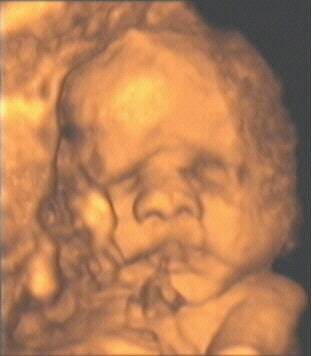

![]() |

| Figure 5, an example of a televised snapshot of the fetus at 28 weeks gestation. Image courtesy of Dr. Stefano Ciatti. |